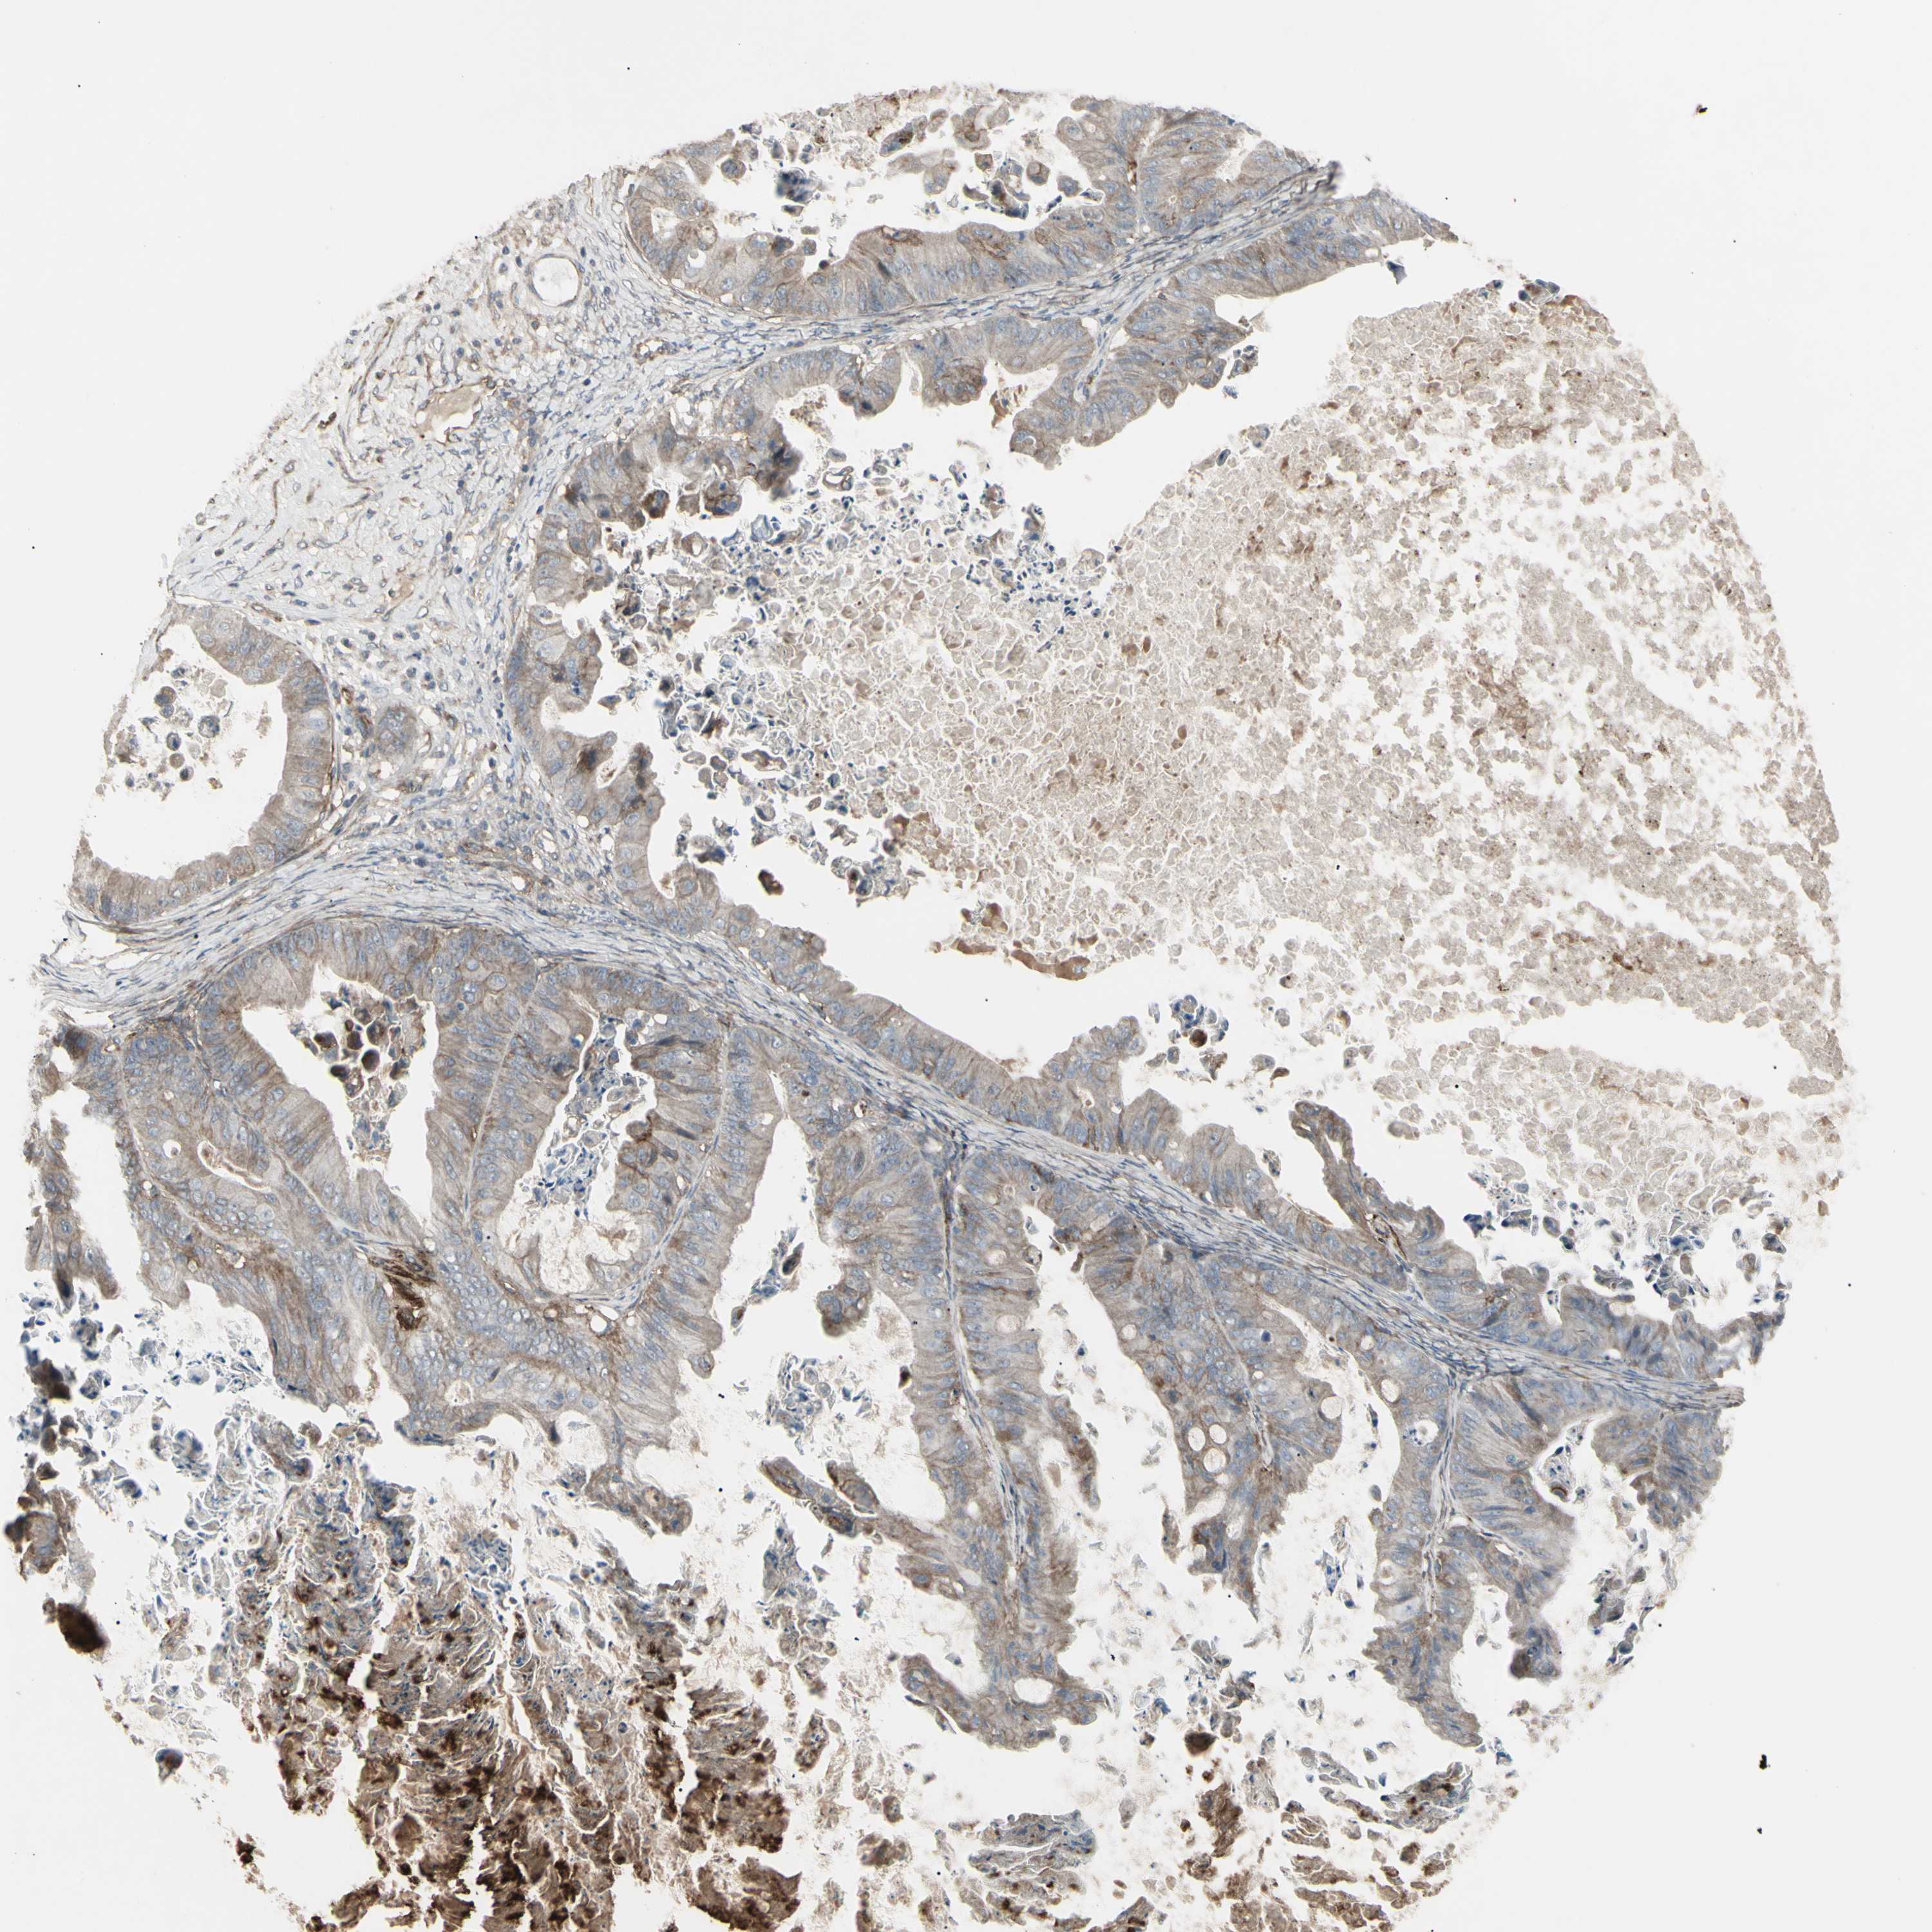

OVARIAN CANCER - Protein expressioni

A mouse-over function shows sample information and annotation data. Click on an image to view it in a full screen mode. Samples can be filtered based on level of antibody staining by selecting one or several of the following categories: high, medium, low and not detected. The assay and annotation is described here.

Note that samples used for immunohistochemistry by the Human Protein Atlas do not correspond to samples in the TCGA dataset.

Antibody stainingi

Antibody staining in the annotated cell types in the current human tissue is reported as not detected, low, medium, or high, based on conventional immunohistochemistry profiling in selected tissues. This score is based on the combination of the staining intensity and fraction of stained cells.

Each image is clickable and will lead to virtual microscopy that enables deeper exploration of all samples and also displays staining intensity scores, fraction scores and subcellular localization as well as patient and tissue information for each sample.

Antibody HPA009285

Antibody HPA017139

Antibody CAB017826

Cystadenocarcinoma, serous, NOS